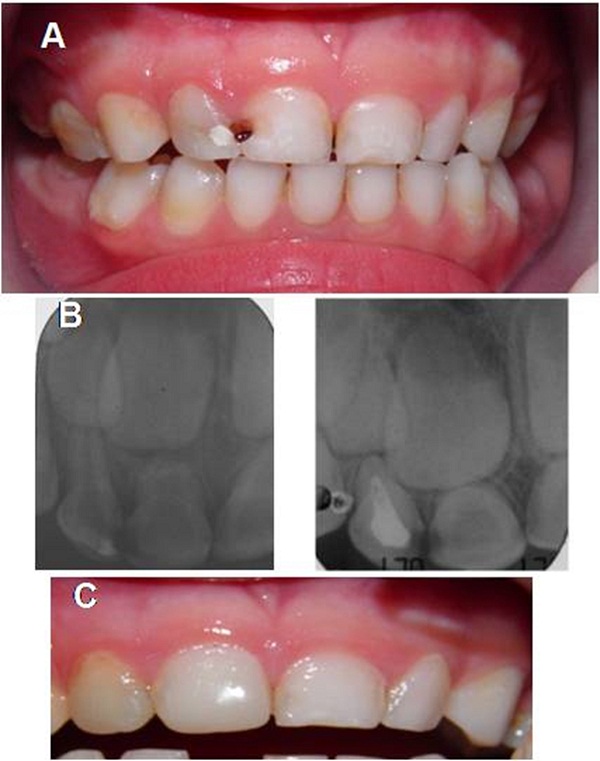

El plan de tratamiento se llevó a cabo por cuadrantes, en orden de prioridad. Al paciente se le rehabilitó el maxilar superior, como puede apreciarse en la figura 3, mediante exodoncia, tratamiento pulpar (pulpotomías y pulpectomías) y restauración con coronas de acero y acetato en el sector anterior (figura 4).

Para la elaboración del mantenedor de espacio se realizó una impresión con alginato en la arcada superior. Posteriormente, sobre el modelo en yeso, se diseñó un mantenedor de espacio removible sin flancos vestibulares y tornillo medio, para acompañar el crecimiento del maxilar. En el arco inferior se hicieron las exodoncias de los segundos molares, la pulpotomía del primer molar inferior derecho, con la adaptación de la corona de acero que se utilizaría como pilar del zapato distal derecho, y una restauración con resina en el primer molar izquierdo (figuras 5a y 5b). Antes de confeccionar los zapatos distales, se adaptaron la corona de acero en el primer molar inferior derecho y una banda con tubo en el primer molar inferior izquierdo (figuras 5c y 5d).